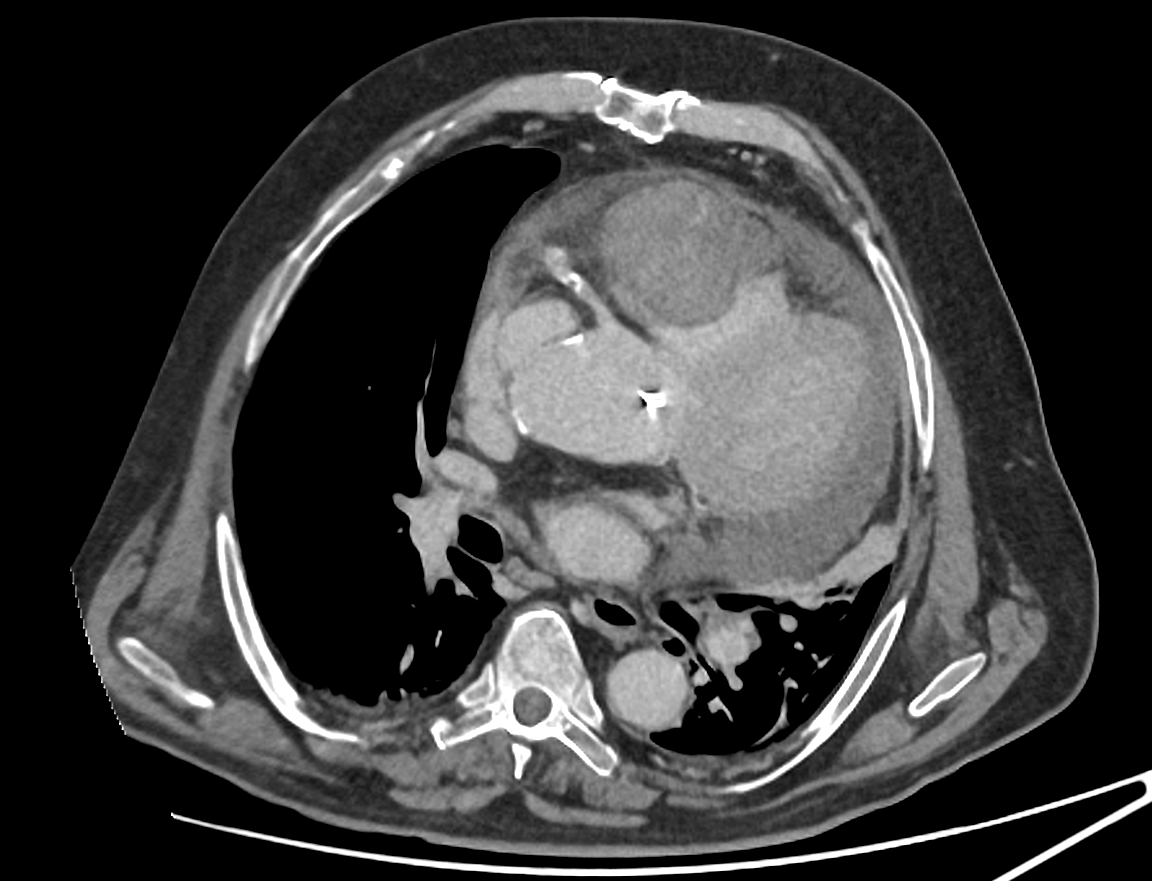

Alors que l'on pensait à une embolie ou une infection chez cet homme avec fièvre et douleurs thoraciques... Le scanner découvre une rupture aortique avec hémopéricarde 😱 Revenons en détails sur les 3 choses essentielles à ne pas rater sur cette coupe, avec petit bonus après ⬇️

Il y a 3 choses essentielles à voir sur cette seule coupe axiale, injectée, acquise au temps portal. Evidemment les 3 sont reliées et permettent de faire le diagnostic global ! Un indice : ce n'était pas ce qui était suspecté par les urgentistes 😅

🤯Un cas très difficile, mais tout est sur cette unique image de scanner : arriverez vous à faire le diagnostic ? Contexte donné par les urgentistes : 72 ans, pneumopathie, mauvaise évolution clinique à J3 du traitement. Recherche EP, surinfection, abcédation. 🤔Vos avis ?